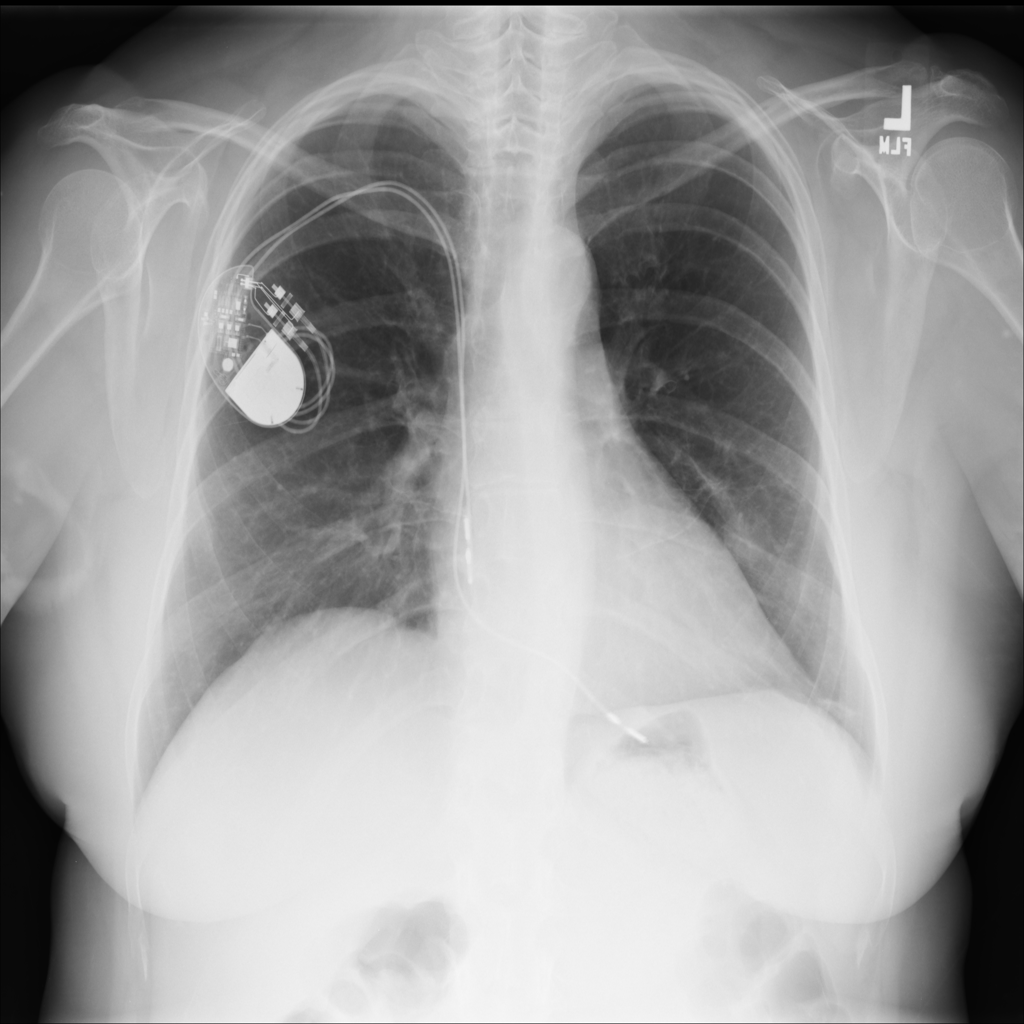

PAT-DB80 · IMG-001Atelectasis

PAT-DB80 · IMG-001

PA